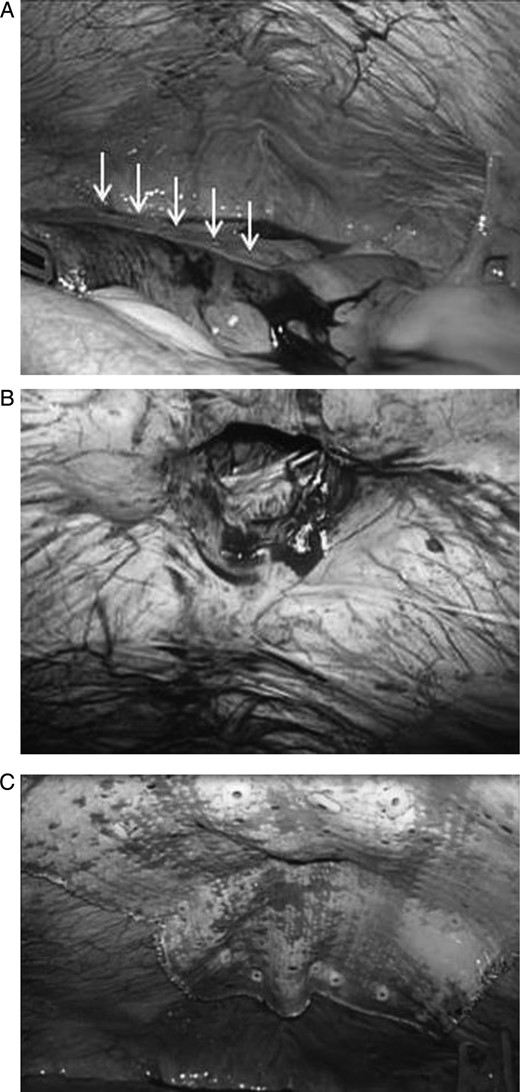

A 42-year-old woman developed an umbilical hernia and left it untreated. Three years later, she was admitted to the emergency room at our hospital with incarceration of the umbilical hernia. The hernia had a size comparable to that of a tennis ball. The patient weighed 75 kg and had a height of 140 cm. Her body mass index (BMI) was 38.3 kg/m2, which is categorized as obese. Computed tomography imaging showed an umbilical hernia with an incarcerated portion of small intestine and a hernial orifice of ∼2 cm (Fig. 1). A gentle attempt at reducing the hernia was unsuccessful; therefore, we decided to perform an emergency operation. After the induction of general anesthesia using a muscle relaxant agent, the hernia was reduced. A 12-mm trocar was inserted just below the epigastric region, and pneumoperitoneum was established by insufflation with carbon dioxide to a 10-mmHg abdominal pressure. Two 5-mm trocars were placed in the right and left lateral abdominal region, respectively. On laparoscopic examination of the abdominal cavity, we identified the portion of incarcerated small intestine. It was reddish and congested; however, there was no evidence of necrosis or perforation (Fig. 2A, arrows). The size of the umbilical hernial orifice was ∼2 × 2 cm (Fig. 2B). We selected a 12 × 12 cm composite mesh (Composix™, DAVOL, Inc., Subsidiary of C. R. Bard, Inc., Warwick, RI, USA) to cover the hernial defect by at least 5 cm in all directions. The composite mesh was inserted through the 12-mm trocar, and it was fixed to the abdominal wall circumferentially by a permanent fixation system (PermaFix™, DAVOL, Inc., Subsidiary of C. R. Bard, Inc.; Fig. 2C). The surgical procedure was uneventful and the total operation time was 112 min. The patient recovered uneventfully and was discharged on postoperative day 9. She remains free of recurrence 20 months after surgery.

(A) The strangulated portion of the small intestine was reddish and congested; however, there was no evidence of necrosis or perforation (white arrows). (B) The size of the umbilical hernial orifice was ∼2 × 2 cm. (C) Composite mesh covering the hernial defect by at least 5 cm in all directions. The mesh was fixed to the abdominal wall circumferentially using a tacking instrument.